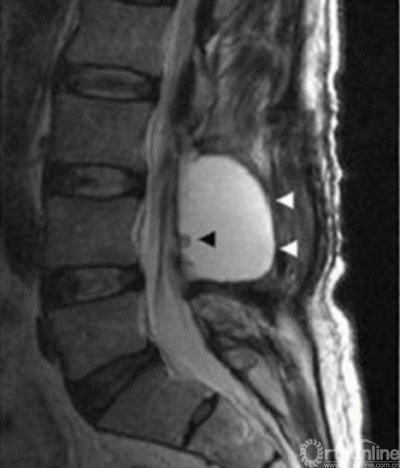

假性硬膜外膨出2

• 筋膜层需要严密缝合,减少深方组织液、血液、脑脊液渗漏到皮下引起切口问题;